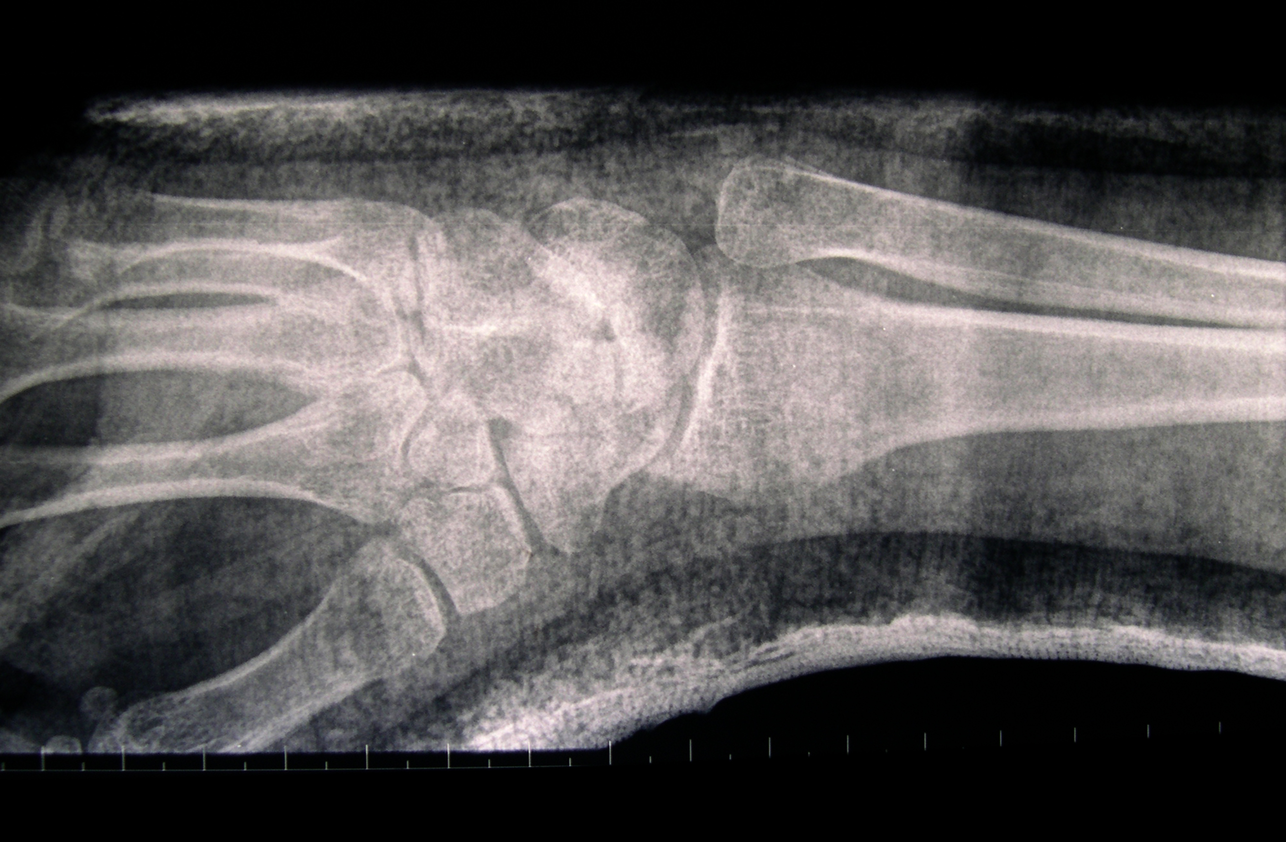

When my arm was in plaster I initially found that the plaster felt supporting because it restricted movement which had been painful. It took over the job on the outside that the bone would have done on the inside, forming an exoskeleton, and by doing so gave the bone the opportunity to heal itself. By the second week the pain had died down and I wanted to be able to move my wrist and thumb but couldn’t. As well as being supported I now felt contained in the plaster; restricted and uncomfortable. After six weeks of not moving my hand it began to ache and I really felt the restriction of not being able to clench my fist. The bones in the hand move in so many directions all of which had been immobilised in the plaster except wiggling my fingers to keep circulation. When the plaster was taken off after nine weeks my hand was rigid and completely immobile, my wrist was locked solid and all my muscles had completely wasted away leaving a bony, shrivelled, scaly, distorted object. I had been looking forward to being able to move it again but the combination of being so stiff and feeling so fragile meant that much of the restriction remained even after the plaster was removed.

Whether the cast on my arm felt supportive or restricting was dependant on the condition of the arm. When the wrist was most injured and needed support then it was a positive experience. Once healed well enough the plaster served as protection from knocks for the new soft bone but also became restrictive. Whilst the plaster supports the bones it also causes the muscle to waste and this creates a conflict between doctors and physiotherapists. The doctor is concerned with the bone rather than the movement and so can be tempted to leave the plaster on too long causing irreversible damage to movement. There is a fine line between providing support and causing damage through restriction. What I find interesting in the tension between the physiotherapist and doctors is that the latter seeks to secure a static structure in repairing the bone whereas the physiotherapist’s purpose is to help restore movement in freeing the joints and rebuilding muscle.